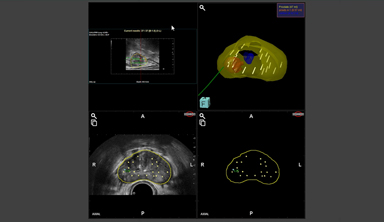

Prostate, Lesion & Urethra

3D wireframe model (1 window)

Needle Pre-planning

Systematic Needles Pre-planning